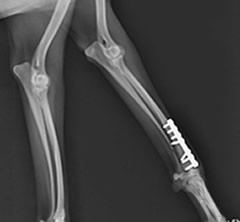

術後:前腕骨骨折整復

プレートとスクリューを使用した強固な内固定術を実施。